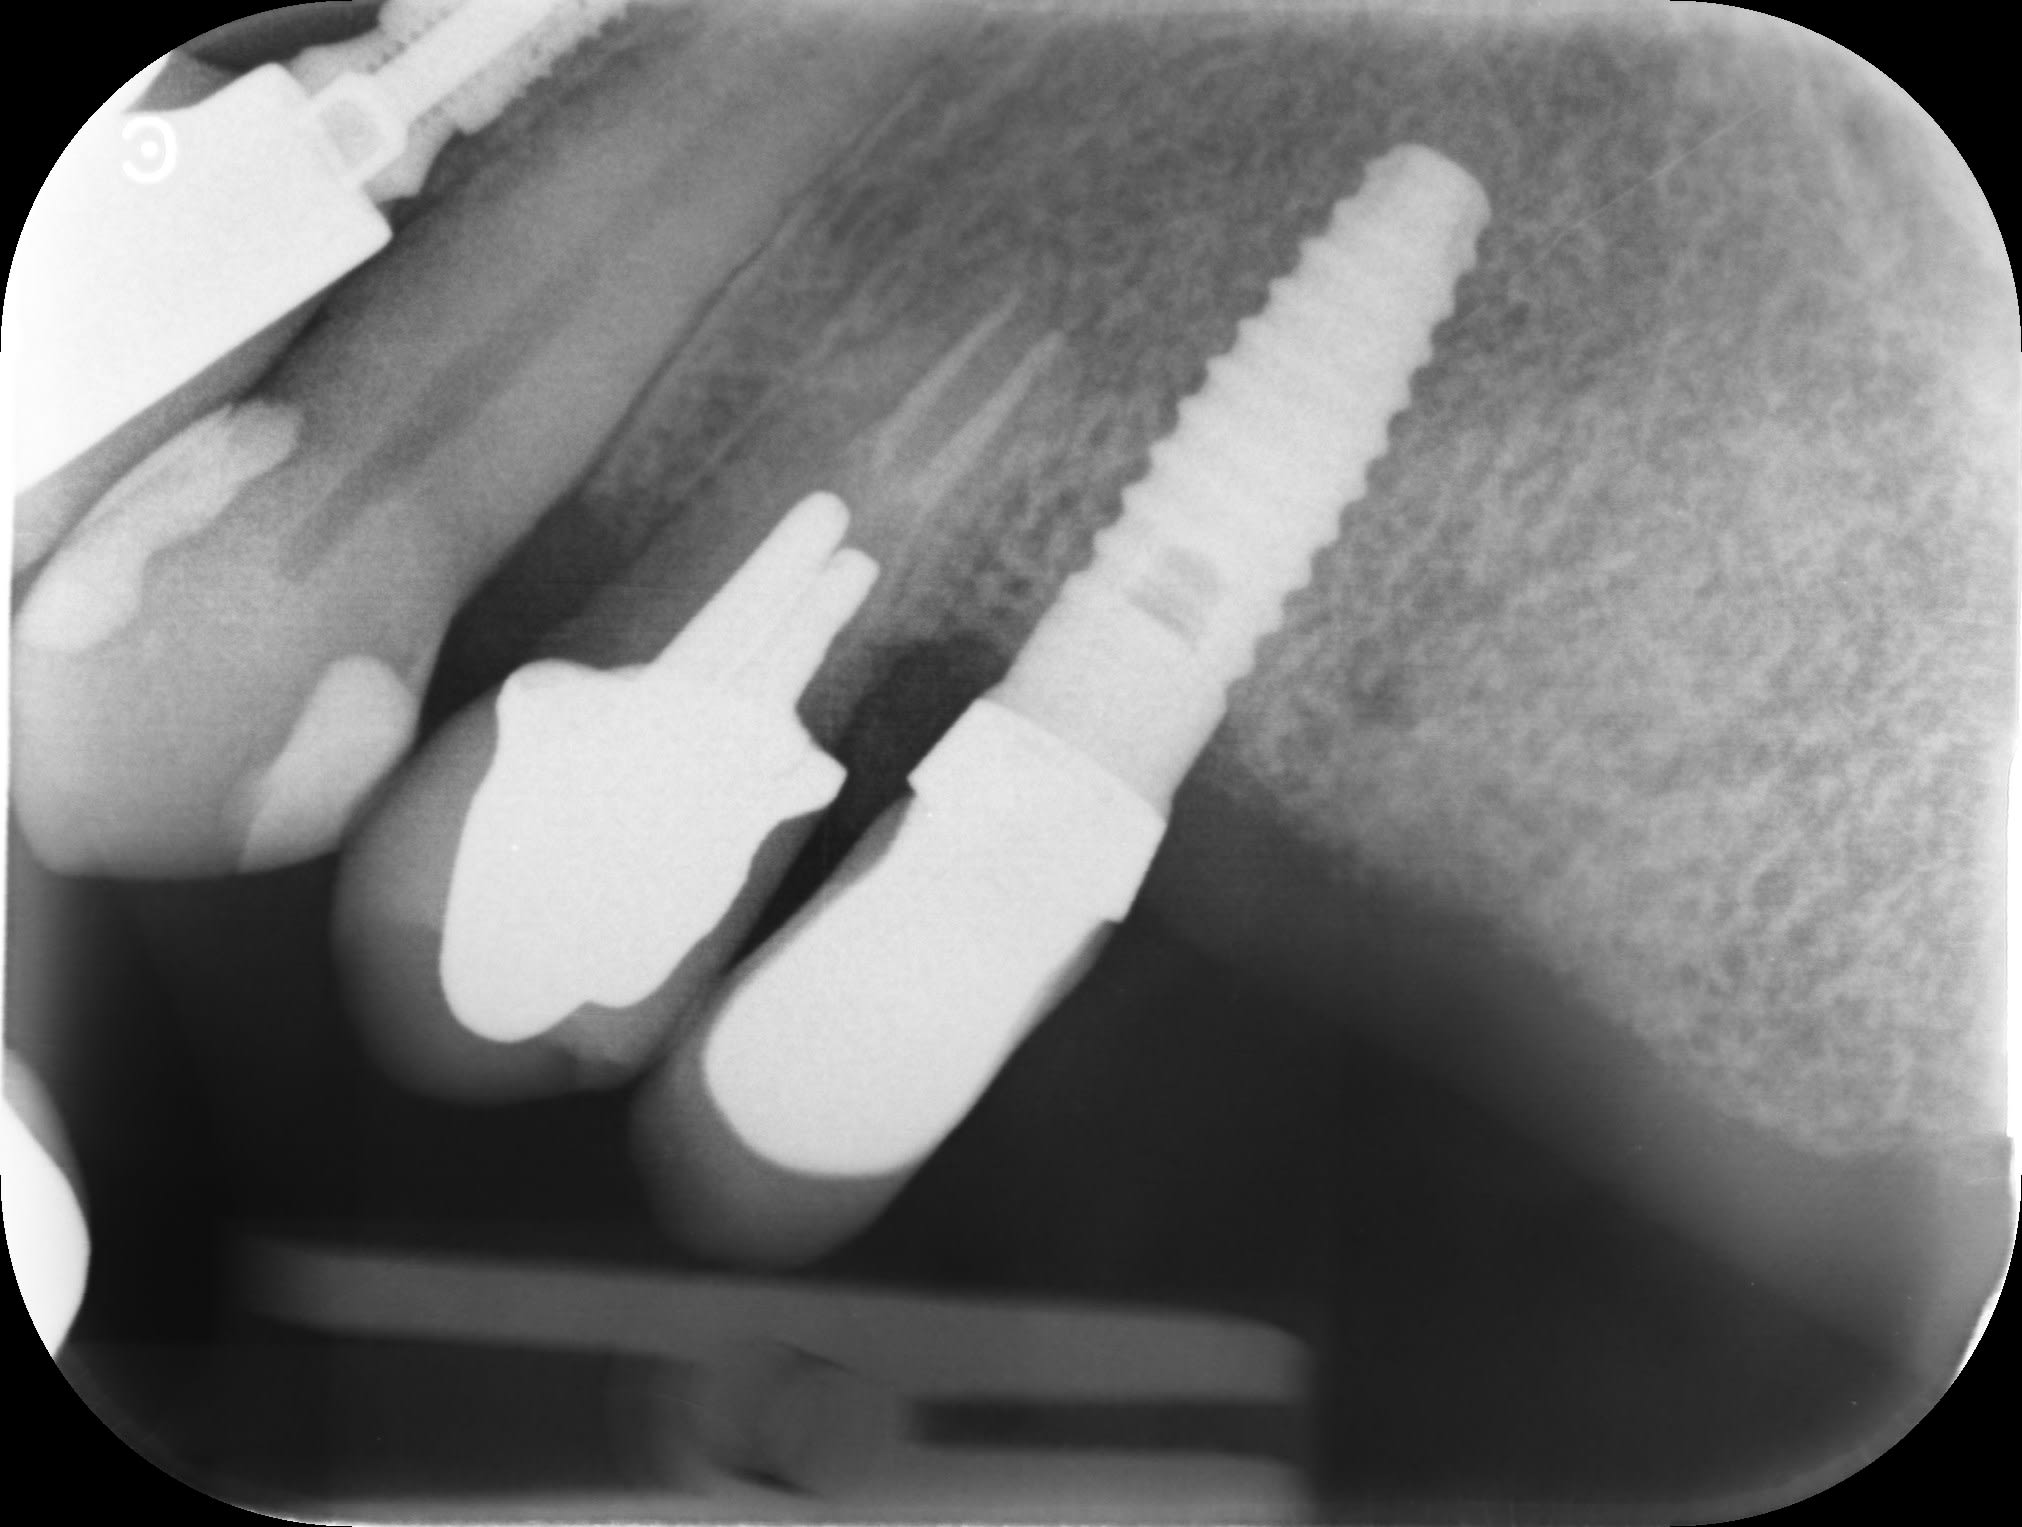

Pouvez-vous m'aider car le patient a poser cet implant 25 à l'étranger.

Impossible de distinguer la connexion ( radio un peu floue et contraste pas idéal sans doute)….trop de correspondances….donc pour l’instant je ne peux pas t’aider

le col est lisse?

Oui effectivement pas facile de faire la distinguer la connexion.

Je vous ai transmis toutes les radiographies que j'ai de cette patiente pour l'implant 25.

bague en zircone forme, Z1 conic ou conect de chez TBR ?

Assez d'accord pour un Z1 conic TBR